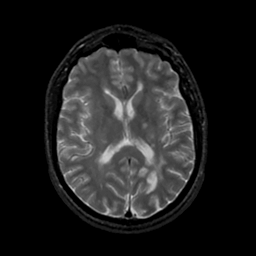

MR Study #18, July 21, 1991 -- Slice #28